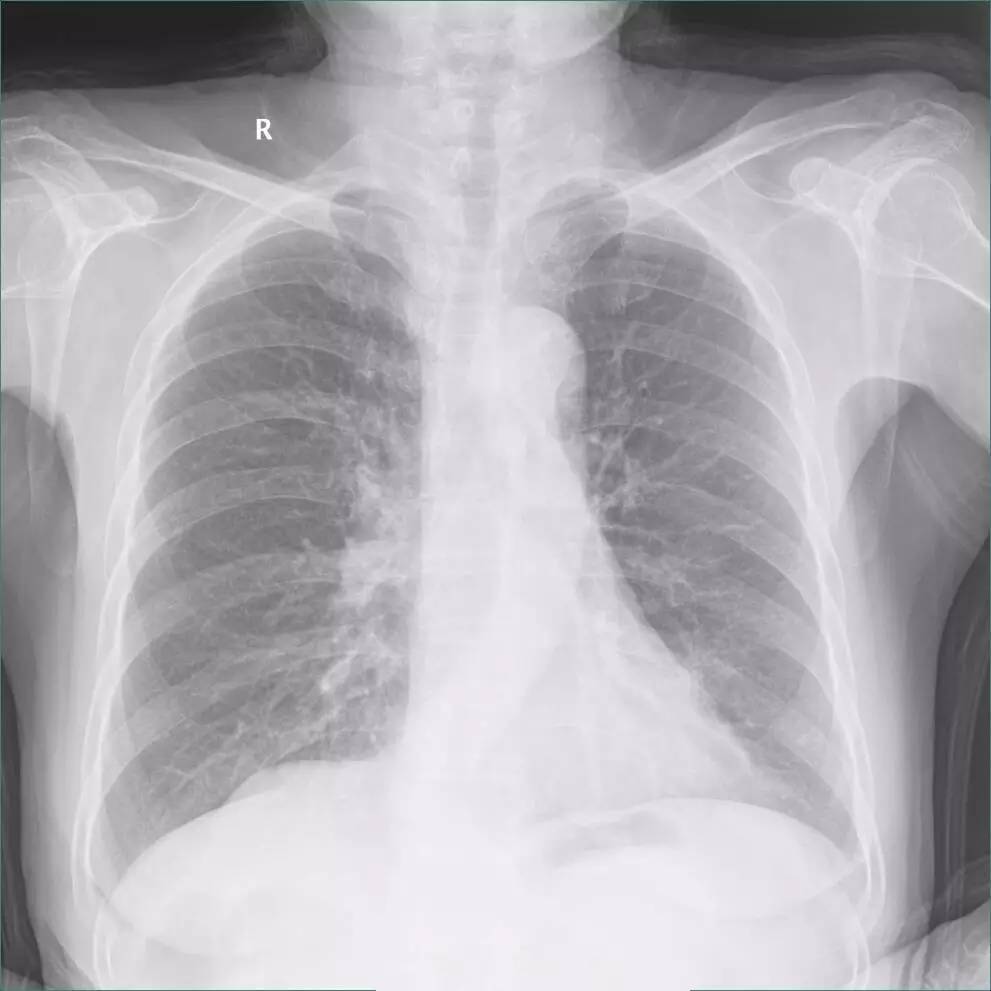

一张二维的胸片中,肋膈角处的异常是胸膜增厚?还是少量胸腔积液,还是模模糊糊分不清?

>>>>病例1:男 82岁 体检,患者自述无任何不适。

左下肺最有可能的诊断是?

A.包裹性积液

B.胸膜增厚

C.胸腔积液

D.心包脂肪垫